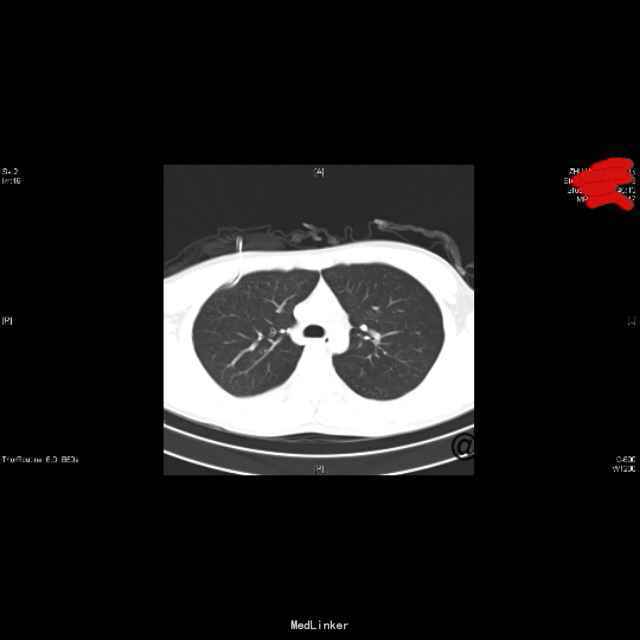

查体:右上肺呼吸音低,余无特殊;心脏、腹部查体未见异常。 辅查: (2015-10-27)行X平片(胸部)检查提示:右侧胸腔引流管置入后改变。 (2015-10-29)胸片:右侧气胸(肺组织压缩约10%),并右侧胸腔引流管置入后改变。 (2015-11-03)行CT(颈胸部CT)检查提示:1、右侧气胸,右侧胸腔积液,右侧胸膜增厚;2、右肺下叶良性硬化性小结节。 (2015-11-09)胸片胸部未见明显异常X线征象。 (2015-10-27)血生化:白介素-69.12ng/L、余无明显异常。 传染病四项、结核感染T细胞检测、大便、小便常规、血常规未见明显异常。 (2015-11-09)复查血常规:嗜酸性粒细胞百分数8.30%、余无明显异常。复查生化:未见明显异常。

诊治经过:患者入院后完善相关检查,排除禁忌后,于10-26行胸腔闭式引流术、置管引流气胸,10-29加负压吸引,11-02予以夹闭引流管24小时,11-03复查胸部CT,阅片示右上肺尖处见少量气体,指示可予拔管处理,继续吸氧。后听诊右上肺呼吸音低,于11-5行床边胸腔抽气术,共抽出900ml气体,予以面罩中流量间断吸氧,11-9复查胸片见右上肺复张。现患者一般情况可,生命体征平稳,经与患者沟通及请示上级医师,给予办理出院。